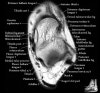

발목 관절의 MRI 단면 영상

- Axial section

Axial PD fat suppression evaluates the tendons and ligaments of the ankle particularly after acute/subacute injuries. It also is sensitive to talar dome osteochondral defects. Alternatively, a T2 sequence can be used to eliminate magic angle artifact that may occur as the tendons travel around the malleolar turns.

Tibiofibular ligaments

Lateral ankle ligaments

Deltoid and spling ligaments

Tendon(Achilles, Medial, Lateral, Anterior)